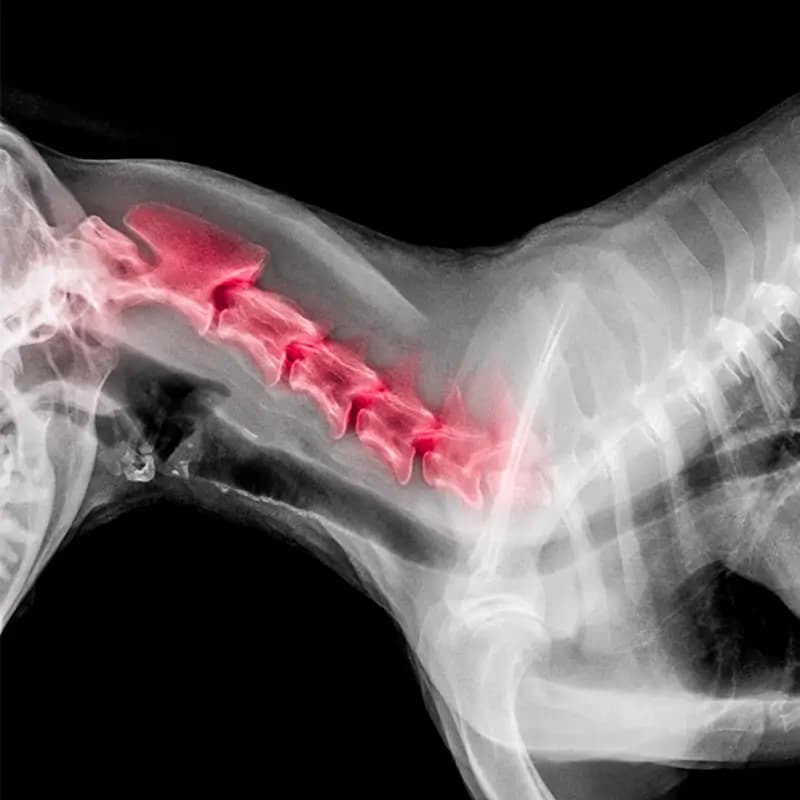

Pathologie